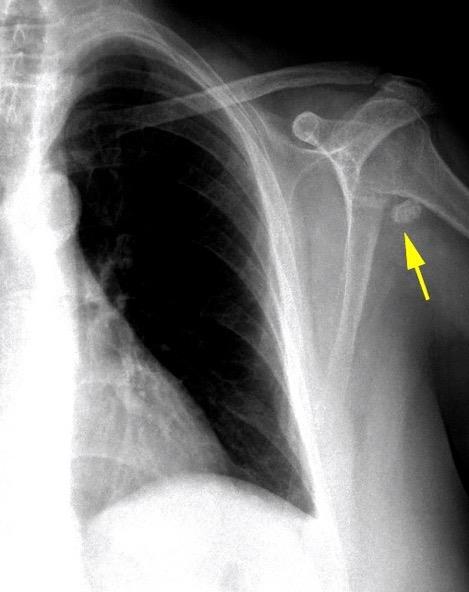

Hallazgo temprano: Osteopenia general. Erosión marginal del borde inferior de la cabeza humeral.

Osteólisis del extremo externo de la clavícula.

Cuomo F et al. THE RHEUMATOID SHOULDER.

Rheum Dis Clin North Am . 1998